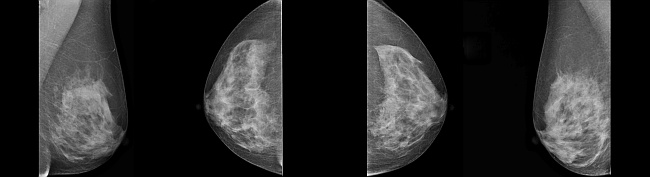

Volldigitale Mammographie mit zusätzlicher Option einer 3D-Tomographie

Funktionsweise der digitalen Mammographie

Bei der digitalen Mammographie wird immer noch ein Röntgenstrahler notwendig.

Durch die Digitaltechnik kann die Strahlendosis reduziert werden.

Vorteil der digitalen Mammographie ist vor allem der bessere Weichteilkontrast bei gleicher räumlicher Auflösung.